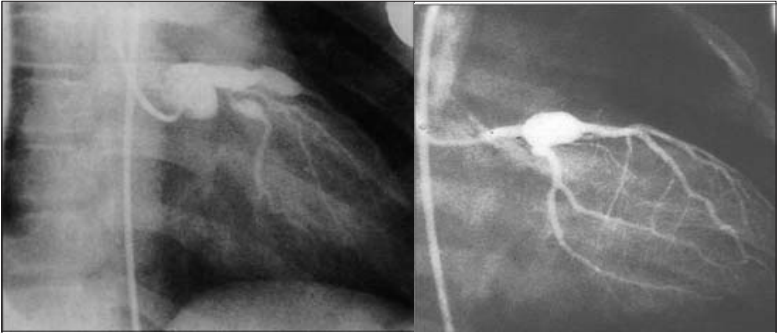

Kawasaki disease has several important clinical consequences, the majority of which are cardiac in nature. Because of this, Kawasaki disease has become the leading cause of acquired heart disease in the developed world.48 The most frequent cardiac complication is the development of coronary artery aneurysms (CAAs).4 (See Figure 6.) These range from small to giant aneurysms based on echocardiography (ECHO) done at initial diagnosis and several weeks later on follow-up. Since the development of 2-dimensional ECHO (1979), it has also been demonstrated that children in the acute phase, while not specifically having aneurysms, can have mild dilation of the aortic root. If not associated with an aneurysm, this dilatation seems to be quite transient, with noted regression of the dilatation even seen as early as one week later.42 When small- to medium-size aneurysms are treated with high-dose IVIG within 10 days of symptom onset, they have shown a high rate of regression (up to 55%).

Figure 6. Coronary Artery Aneurysms

Injection of the left coronary artery demonstrates two large, saccular aneurysms in the proximal left anterior descending and circumflex coronary arteries. Coronary artery aneurysms may develop in 15-25% of untreated Kawasaki disease patients.

Coronary artery aneurysms can occur in up to 25% of patients. Therapy options (see the Treatment section) include IVIG and aspirin, which are given in conjunction to prevent the progression to coronary artery aneurysms. The prevalence of CAAs can be reduced to approximately 4% with the use of these medications.49 Much has been discussed about the proper timing of therapy aimed at preventing and treating these aneurysms. While it remains true that therapy should be instituted within 10 days, some literature reveals that aneurysms can develop as early as day 7 of symptoms onset.48 Given this finding, it would be ideal to confirm the diagnosis before day 7 of symptoms, not day 10 as previously considered, and begin therapy.